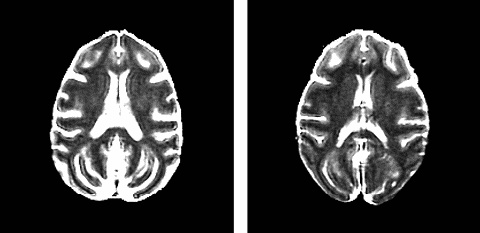

Результаты сканирования мозга двух пожилых макак – обычной и на диете. Хорошо видно, что у макаки, которая получала полноценную, но низкокалорийную диету, сохранился больший объём серого вещества.

Неудивительно, что макаки на диете имели меньший вес, гораздо интереснее другое: результаты магнитно-резонансного сканирования показали, что количество серого вещества в их мозгу превышало таковое у контрольной группы. «Объёмы отдельных участков мозга с возрастом практически не изменились. Это явление нельзя назвать повсеместным. Однако данное открытие определённо поможет нам определить, влияет ли диета на потерю нейронов», – поясняет нейробиолог Стирлинг Джонсон.

Несмотря на то что нетронутыми оказались области, отвечающие за регуляцию движений, а также за память и решение определённых задач, исследователи пока не могут сделать выводы о последствиях такого различия. Дело в том, что они ещё не сравнивали когнитивные способности выживших животных.

«На данный момент мы можем говорить лишь о наблюдаемых различиях объёма участков мозга, вероятно, связанных с низкокалорийным рационом», – добавляет Джонсон.